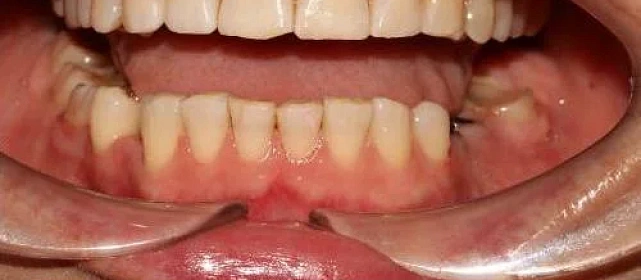

Нарушение соотношения челюстей и неправильное положение зубов — ряды смыкались некорректно, зубы стояли со смещением.

Металлические самолигирующие брекеты H4 на обе челюсти. Выровнять зубы, исправить прикус, подготовить к установке коронок. Срок — около 2,5 лет.

Прикус исправлен, зубы выровнены. Установлены несъёмные ретейнеры на обе челюсти, после установки коронок будут изготовлены ретенционные капы.